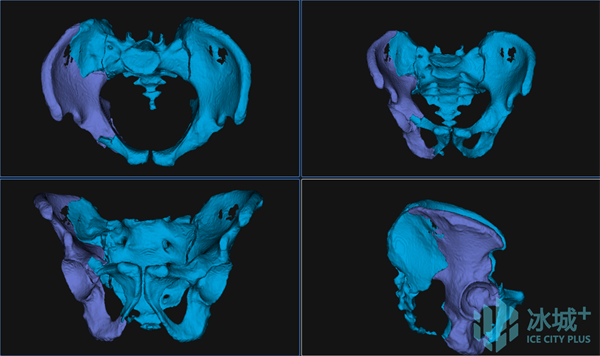

图2 自动分割与重建

术前,刘建宇教授团队充分讨论,采用目前全球最先进的智能化骨科手术机器人全流程辅助骨盆骨折闭合复位内固定手术治疗。基于患者术前影像,借助基于AI与大数据的自动手术规划,将患者健侧肢体进行镜像配准,通过精细化自动分割与重建,实现个性化、定量化的复位规划。